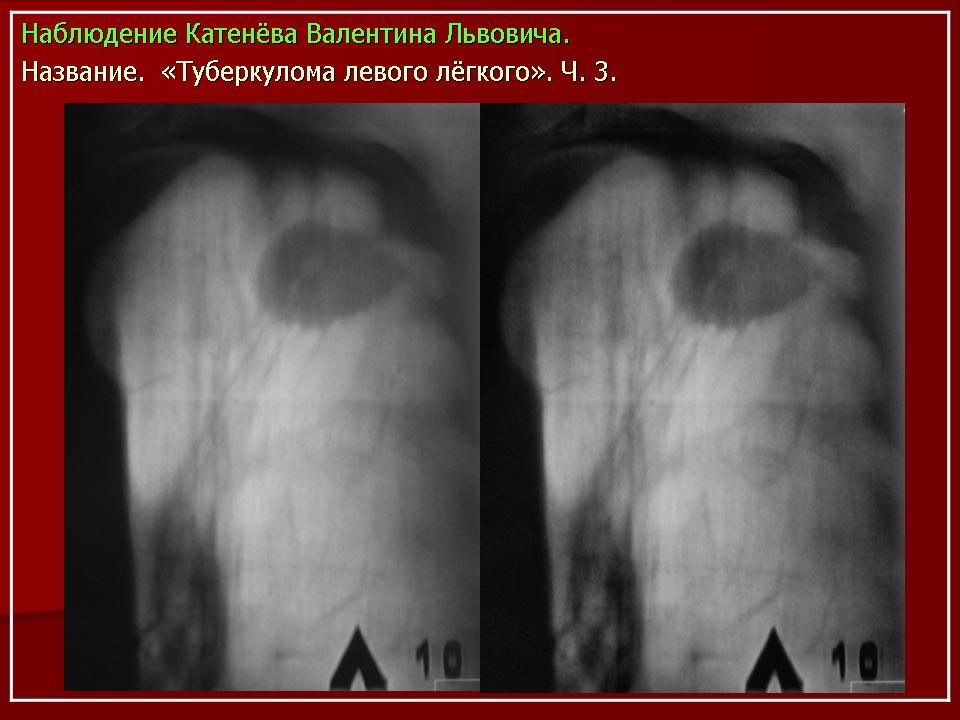

Обзорная рентгенограмма органов грудной клетки в прямой и правой боковой проекции.

В прикорневом отделе левого легкого отмечается малоинтенсивное уплотнение легочной ткани.

Фрагменты комтьютерных томограмм левого легкого

В S6 нижней доли левого легкогоу медиальной стенки субсегменарного бронха выявляется неправильной формы, неоднородной структуры фокус уплотнения размерами 1,9х1,0 см с редкими короткими тяжами в легочную ткань и к медиастинальной плевре. Легочный рисунок в прилежащих отделах деформирован.

Туберкулема нижней доли левого легкого.

Высокоразрешающая КТ. В толще фокуса уплотнения отчетливо выявляются известковой плотности включения и рубцовая деформация субсегментарного бронха.